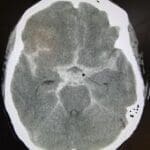

SAH